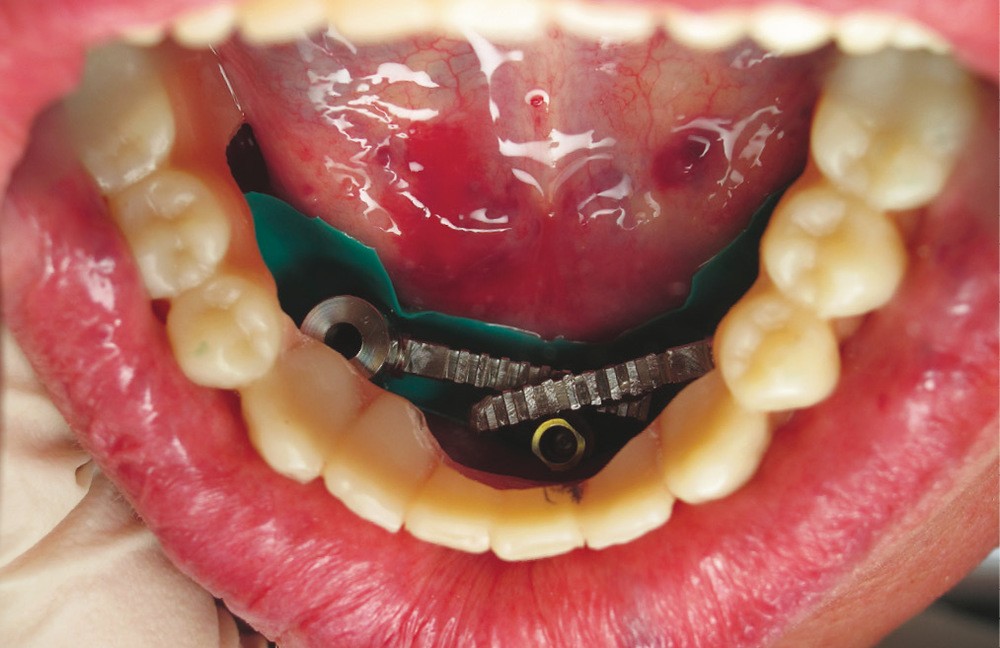

La phase chirurgicale démarre avec une levée de lambeau puis une régularisation crestale afin d’offrir un « large » plateau osseux. Les forages sont assurés par le guide de première intention suivi des différents guides de la trousse Trefoil (fig. 4). Un premier essai est concrétisé : la barre est vissée puis la prothèse est insérée pour contrôle d’absences de contraintes entre les parties. Des meulages sélectifs sont possibles.

Après sutures, une digue de protection est positionnée à la base des transferts d’empreinte, qui sont ensuite indexés avec une résine type PiKu Plast. La prothèse est replacée puis solidarisée à la clé d’indexation implantaire, après vérification de l’occlusion (fig. 5). Une injection en silicone parfait l’enregistrement des tissus mous. L’ensemble est dévissé et transmis au laboratoire pour finition. Vissage des analogues et coulée de l’empreinte procurent une réplique au laboratoire de la situation clinique.

Après démontage et nettoyage du dispositif implantoporté, la barre Trefoil est vissée passivement [7] sur ses analogues grâce à un mécanisme judicieux de rotules compensatrices. Un dernier contrôle de coaptation barre/prothèse est réalisé (fig. 6). L’ensemble est sablé et solidarisé par une résine chémopolymérisable. Après polymérisation, suppression des extensions, aménagement des accès prophylactiques et maquillage composite par addition acté, le bridge d’usage est mis en charge immédiatement (fig. 7).